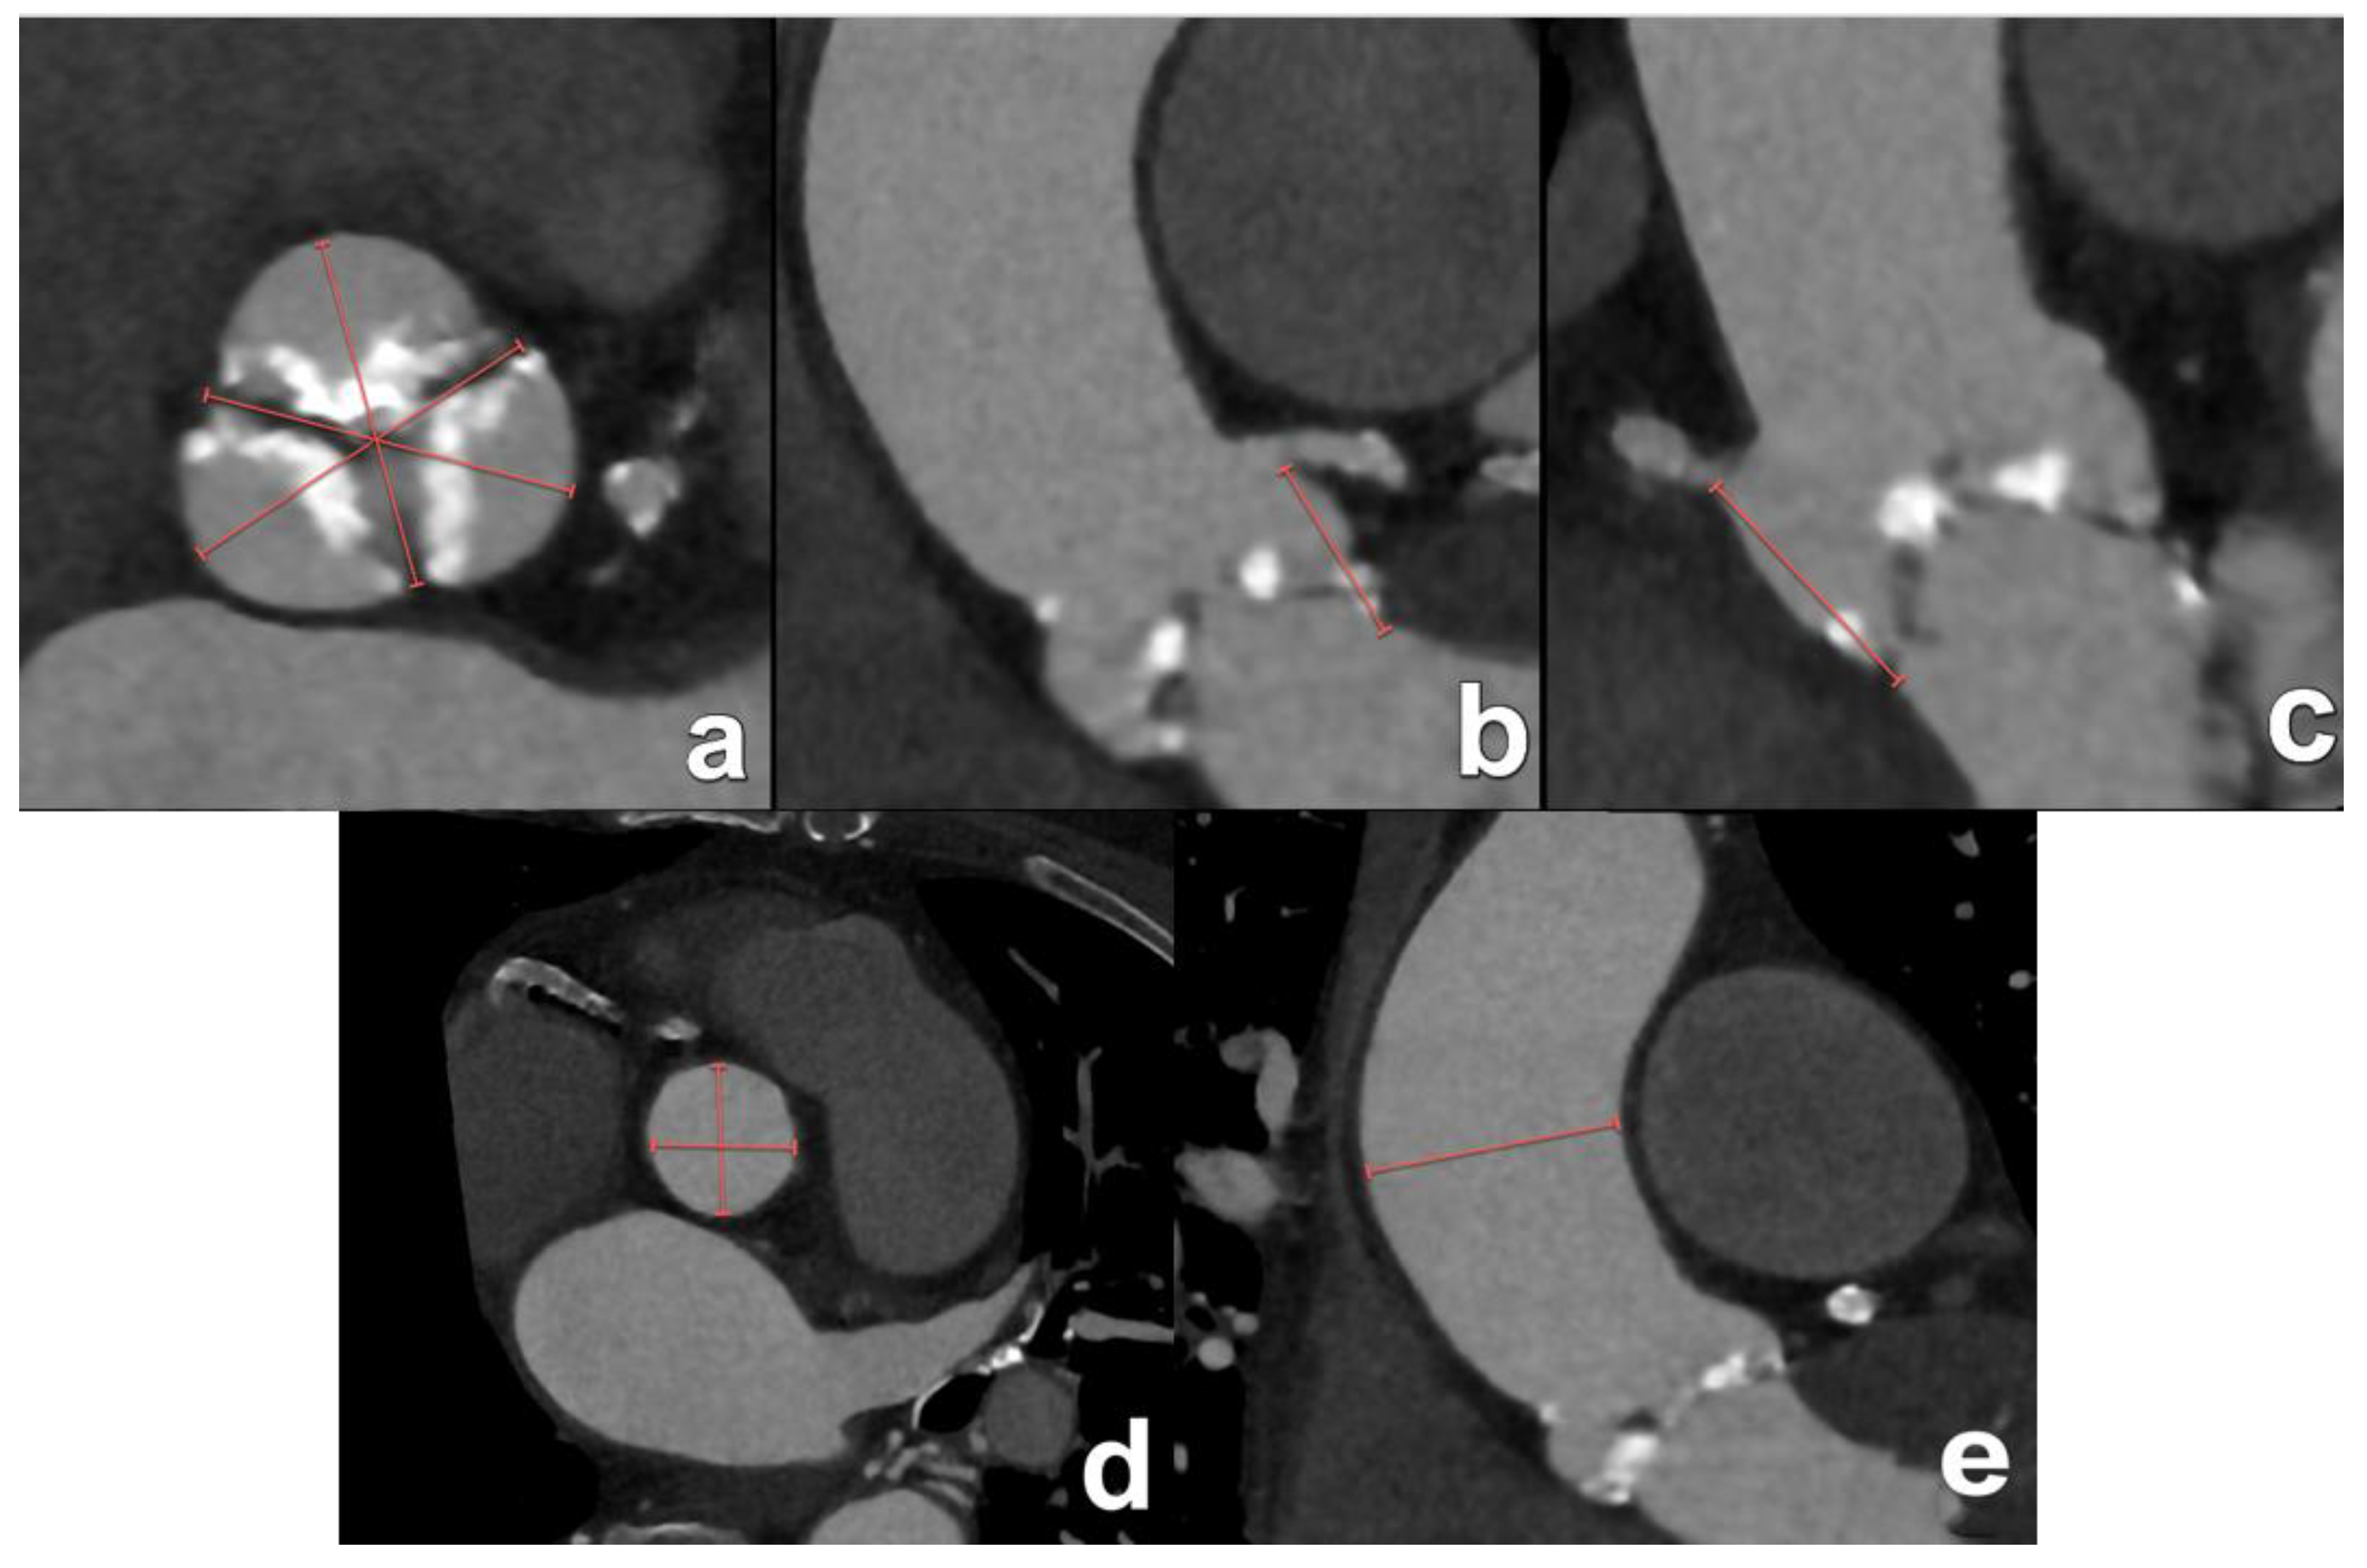

| Aortic annulus dimensions | Long- and short-axis diameters Area Perimeter | Sizing algorithms are device- and manufacturer-specific. |

| Aortic valve cuspidity | Comment on number of leaflets | The presence of a bicuspid valve may increase procedural complexity and increase the risk for permanent pacemaker implantation after the procedure. |

| Coronary ostia heights | Distance from annular plane to bottom of left and right coronary ostia | As a rule of thumb, a minimum diameter of 10 mm is considered the threshold to avid ostial coronary obstruction by migrated leaflet calcifications. |

| Sinus of Valsalva dimensions | Long- and short-axis cross-sectional diameters Largest cross-sectional diameter Commissure-to-cusp diameter Height of the coronary sinus | The aortic sinus needs to be wide enough to accommodate displaced native leaflet calcifications during the deployment of the THV. |

| Sinotubular junction diameter | Diameter at the sinotubular junction | |

| Tube angulation | Angles of the tube where all basal insertion points of the aortic leaflets are aligned in one plane | Knowledge of this tube angulation can reduce procedure time and the use of contrast material. |

| Ascending aorta diameter and wall calcifications | Diameter at 40 mm above annulus Presence and severity of aortic wall calcification | For transaortic access, the landing zone is about 60 mm above the annular plane. |

| Left ventricular outflow tract and subvalvular calcifications | Long- and short-axis diameters | The presence of prominent subvalvular calcification may interfere with THV deployment. |

| Aortic valve calcification | Quantification and distribution of leaflet calcification | The Agatston score is used to quantify leaflet calcifications. This is not routine and typically reserved for low-flow low-gradient cases with inconclusive echocardiography results. |

| Left ventricular basal septum thickness | Presence of basal left ventricular hypertrophy | A hypertrophic basal septum may contribute to device instability. |

| Peripheral access vessel diameters | Minimal luminal diameters of the iliofemoral arteries | A minimal luminal diameter of 5–6 mm is generally required, depending on the delivery system. |

| Aortic angulation | Angle between the LVOT and ascending aorta planes | A steep angulation increases procedural complexity. |